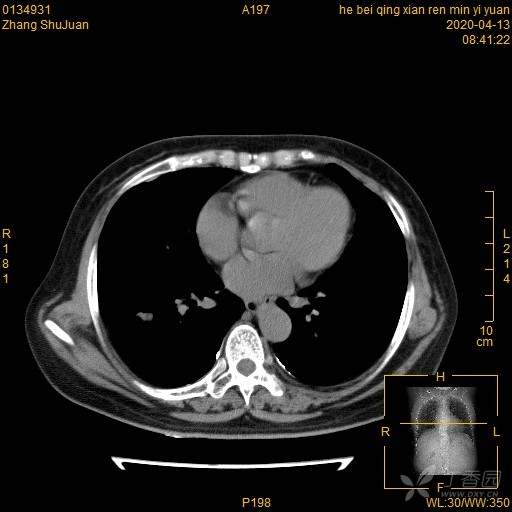

右肺结节猜病理,有结果(得细心,这个很有意思)(俱乐部3)

西门开心 +5 丁当患者性别:女

患者年龄:49

简要病史:体检发现右肺结节,不吸烟。

体格检查:无阳性体征

辅助检查:血常规、血沉正常,血肿瘤标志物正常。FET-CT倾向恶性结节

临床诊断:右肺结节

治疗经过:手术

大家猜猜病理是什么?